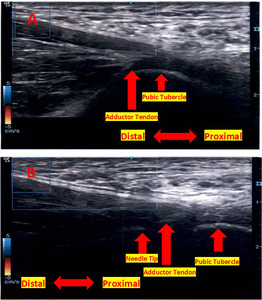

Ultrasound-Guided Platelet-Rich Plasma Injection

The Arthrex Angel System (Naples, FL) was utilized to deliver platelet-rich plasma. The max centrifuge spin was 4000 RPMs with a starting volume of 60 ml of the patient’s own blood and a hematocrit setting of 4%. There was an average fold yield increase of a 5.76 platelet (PLT), 1.69 white blood cell (WBC), and .67 neutrophil (NE) obtained in PRP preparation relative to whole blood. Cellular concentrate included a PLT concentration of 1032.94 k/µL, WBC concentration of 8.55 k/µL, and a NE concentration of 1.81 k/µL. The adductor was identified with ultrasound, and a doppler was used to evaluate for any adjacent neurovascular structures. The injection site was cleansed with chlorhexidine, and sterile gel was applied. 5 ml of 1% lidocaine and 1 mL (40 mg/mL) of Depo Medrol were delivered through the 22-gauge 3 ½ inch needle into the adductor tendon. Subsequently, 5 ml of PRP was delivered through a 20-gauge needle. (Figure 2A &B) Risks, including infection, bleeding, nerve damage, and pain at the injection site were thoroughly discussed with the patient.